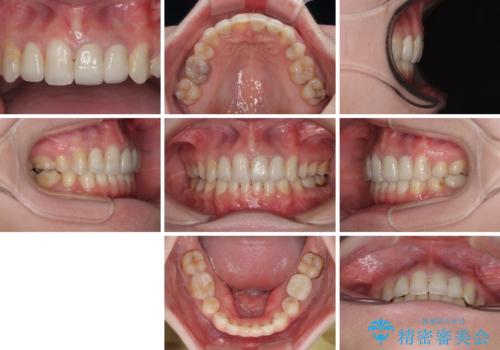

気になっていたむし歯と前歯のデコボコ 矯正治療とむし歯治療の総合歯科治療

- 前歯のデコボコと、その結果むし歯が進行していることを気にして来院された患者様です。

前歯や奥歯の根管治療を行い、その後上下左右の第一小臼歯4本を抜歯してワイヤー装置にて矯正治療を行うこととしました。

矯正治療後には、根管治療を行った歯をオールセラミッククラウンにて補綴治療を行うこととしました。

治療途中で激務の会社に就職することとなり、なかなか矯正治療に通院することができなくなり、治療期間が想定の2倍近くとなりましたが、無事に満足のいく形で治療を終えることができました。